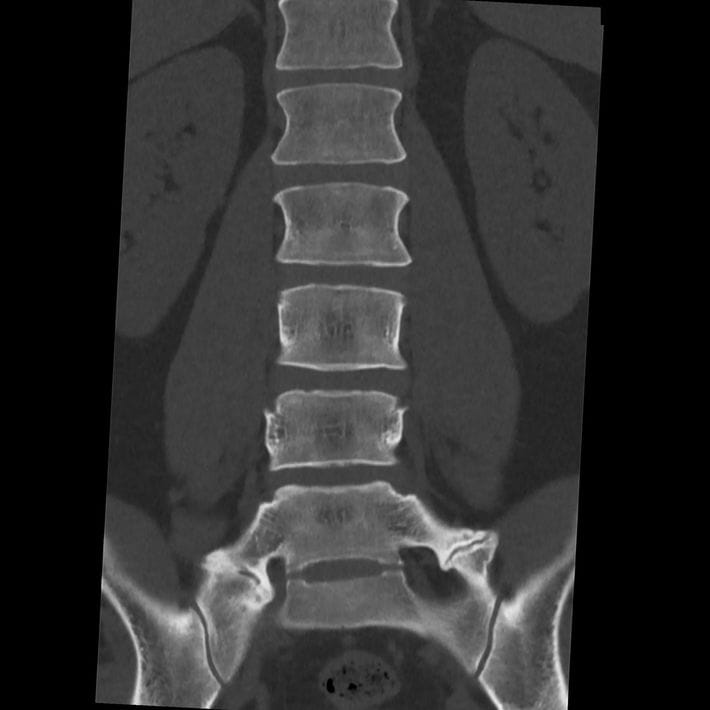

一般的に骨の形や配列、変形を詳しく調べるためCTを撮影する。この画像では一部に腰痛の原因となる可能性がある所見が認められた。(『

カニジル 18杯目

』より)